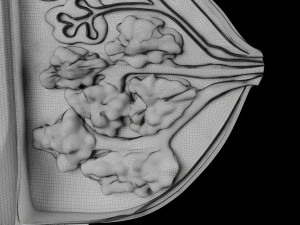

Breast anatomy histology detailed labelled precise to scale model 3D Модель

This is a 1:1 scaled model of right breast cut opened in sagittal plane to reveal its internal antomy and histology (schematic). The deeper parts and fascial layers are also depicted to give a very detailed approach to the model. The full layers starting from skin, nipple areola, till intercodtal muscles and ribs are also depicted.

breast mammary gland female chest wall anatomy human medical science reproductive genitalia muscle fascia milk nipple areola subcutaneous fatДо даного товару немає коментарів.